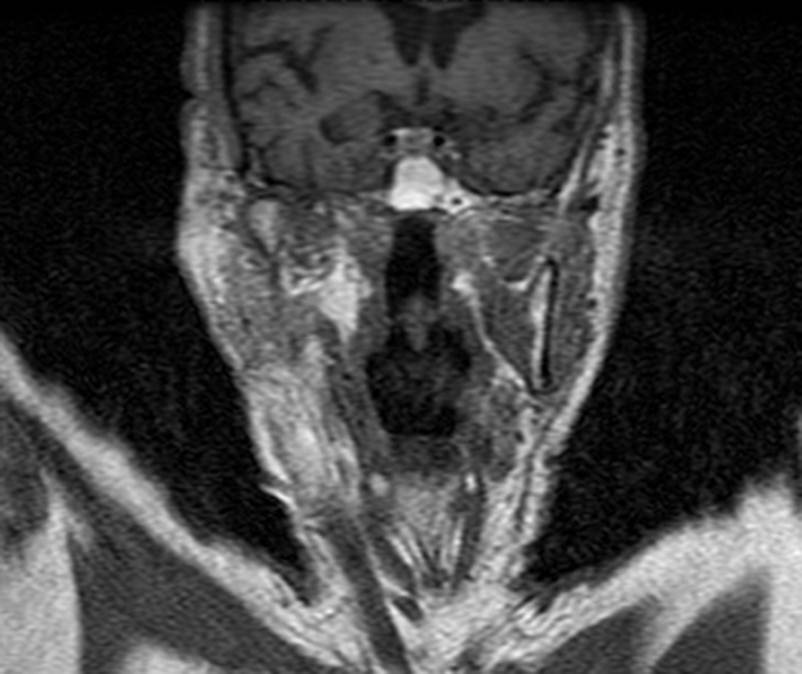

CT: Brain Atrophy